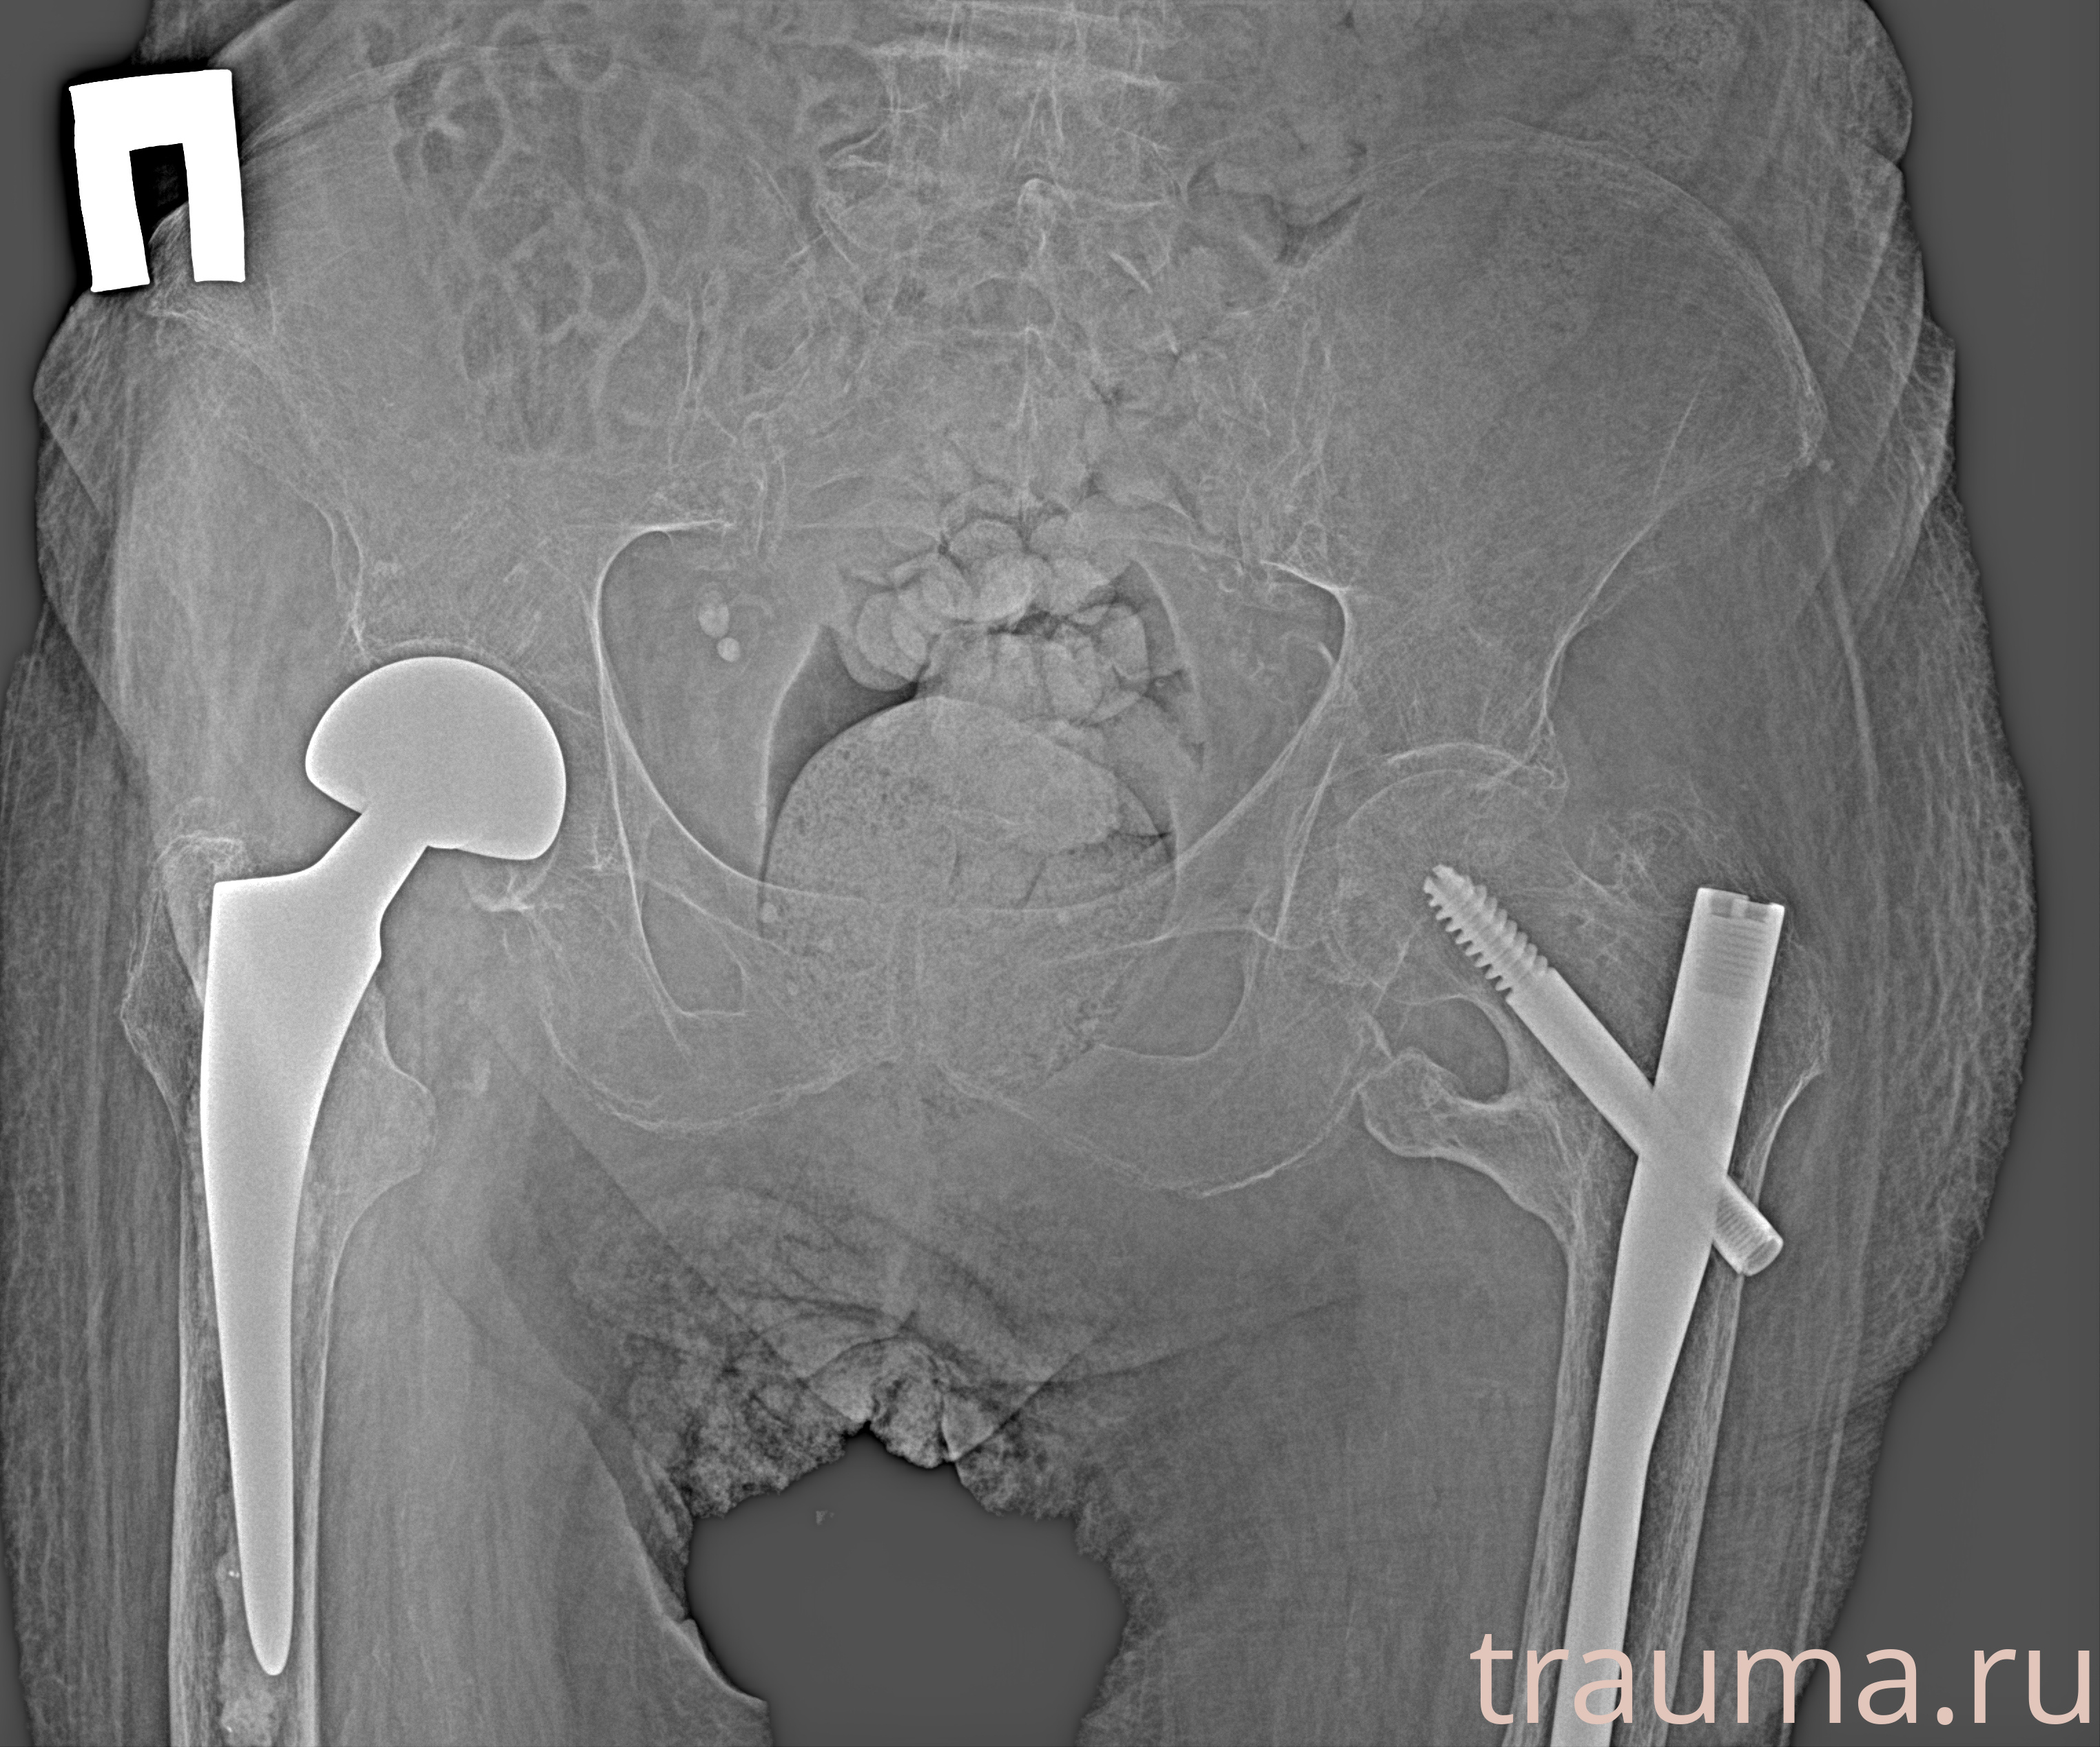

Рентген на дому: по вашему адресу приезжает врач-рентгенолог, травматолог-ортопед с мобильным рентгеновским аппаратом, проводит диагностику травмы или заболевания, делает необходимые рентгенограммы, дает рекомендации по дальнейшему лечению. Получить качественные снимки в домашних условиях возможно благодаря уникальной методике, разработанной МосРентген Центром для института  Склифосовского